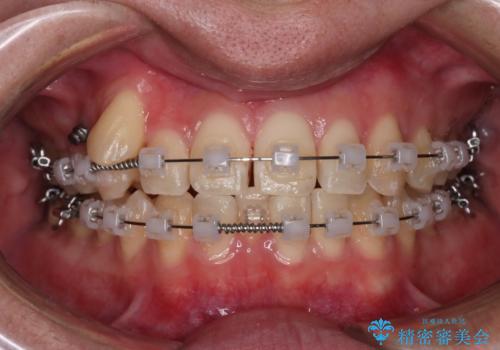

【クリア装置】八重歯とがたつきを綺麗に

- クリア装置

- 上の八重歯と下の歯のがたつきを主訴に来院されました。

矯正検査の結果、抜歯はせずに

臼歯を遠心移動させ、歯列をワイヤーで整えることでスペースを確保し、IPR(歯と歯の間を削る処置)を加えて歯並びを綺麗にする治療計画を立てました。

歯の移動にオープンコイルとMI(歯肉に埋入するネジ)を用いました。

非抜歯矯正だったこともあり、1年半以内という短い期間で矯正を終了することができました。

気にされていた八重歯とがたつきが綺麗に改善されました。